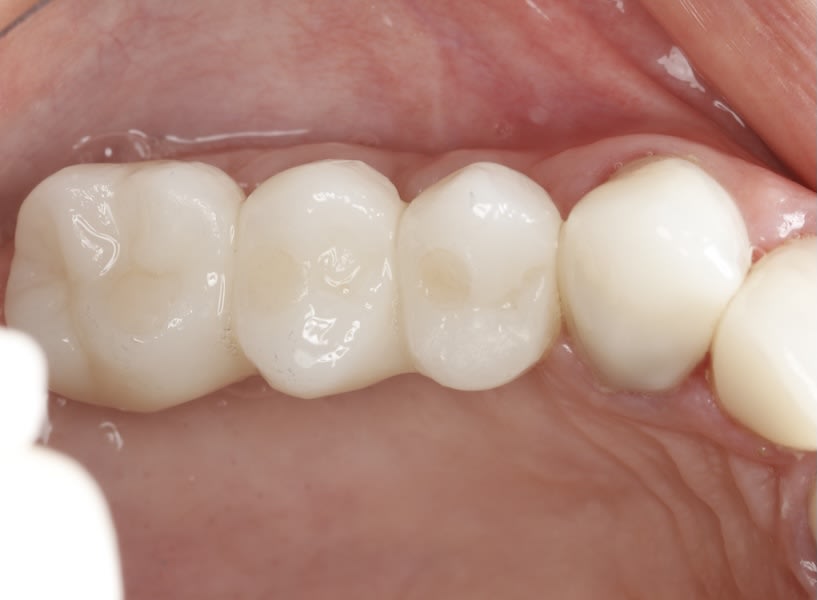

Case 1 (Figure 3 through Figure 24) depicts a 3-year follow-up of combined osseodensification sinus protocol IV in a severely resorbed maxillary ridge with ≤0.5 mm bone height in molar sites and horizontal deficiency at the first premolar site, using a two-stage approach for implant placement.

Case 2 (Figure 25 through Figure 36) illustrates a 3-year follow-up of the osseodensification sinus protocol IV in a severely resorbed right maxillary ridge with <0.5 mm bone height in molar sites, using a two-stage approach for implant placement.

Case 3 (Figure 37 through 44) shows a case of significant trauma history with a 3-year follow-up of the osseodensification sinus protocol IV in a severely resorbed right maxillary ridge with ≤0.5 mm bone height in molar sites, using a two-stage approach for implant placement.

The presented protocol describes a crestal sinus elevation procedure using osseodensification burswith vertical stops (Versah) in severe cases with <2 mm of residual bone as a predictable technique, with successful bone regeneration for second-stage implant placement with subsequent stable peri-implant bone level at 3-year follow-up. This technique, thus, offers a simplified, minimally invasive, and less traumatic method for sinus floor elevation in cases with severe residual bone height loss.